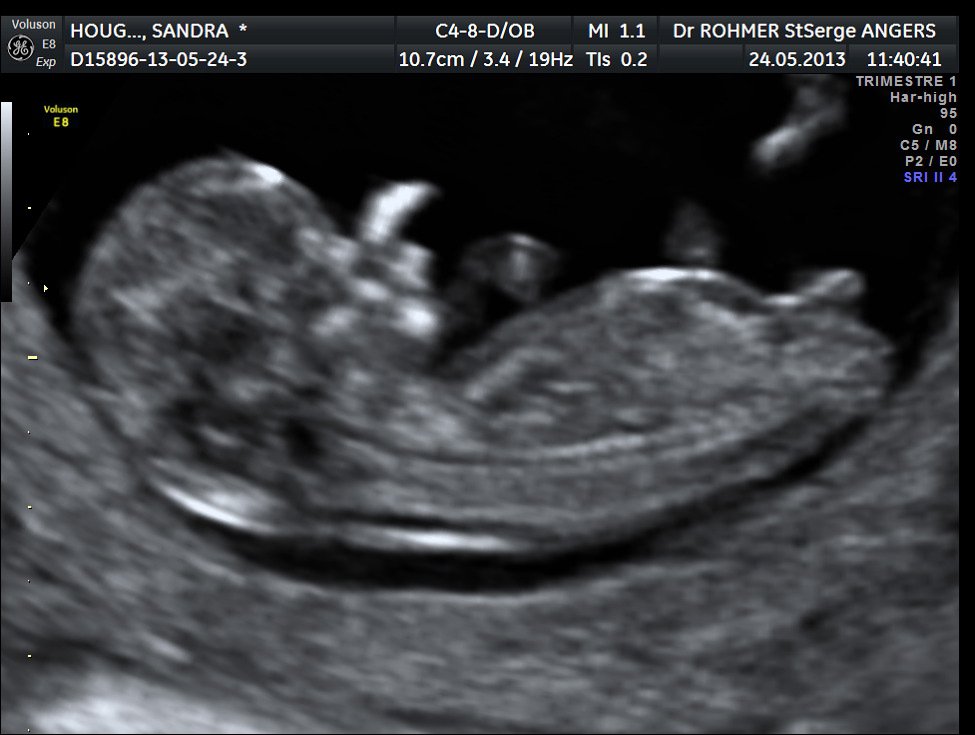

A partir de la 14e ou 15e semaine de grossesse, le ou la gynécologue est en mesure de reconnaître distinctement le sexe du bébé à l'aide d'une échographie Les organes génitaux seront alors visibles sur l'écranQue des histoires de grandsmères et des mythes étranges, mais de quoi passer le temps avant le grand jour!Actuellement il ne faut pas déterminer le sexe fœtal à partir du tubercule génital avant 12 SA car le taux d'erreur est de 40 % et donc ne dépasse que de peu l'effet du hasard l'aspect est dit féminin quand le le tubercule génital part vers le bas et horizontalement l'aspect est dit masculin quand le tubercule génital part en avant et

Ce test peut être demandé quand il y a un risque de certaines maladies génétiques touchant un sexe ou l'autre", précise le gynécologue Quand savoir le sexe de son bébé ?Selon la « nub theory » ou méthode du bourgeon génital, on peut, dès 12 semaines d'aménorrhée environ, avoir une idée du sexe de bébé en étudiant l'angle entre le bourgeon et la colonne vertébrale Chez un garçon, le bourgeon forme un angle d'approximativement 30 degrés avec la colonne vertébraleLe 05h52 Lecture en 3 min L'annonce du sexe du bébé se fait lors de la seconde échographie, entre la e et la 22e semaine de grossesse Mais tout dépend de la façon dont les organes génitaux se développent et du bon vouloir de bébé qui accepte, ou non, ce jourlà de dévoiler son sexe Sexe de bébé rien de

Il y a à peine quelques années, l'échographie était le seul procédé offert aux femmes enceintes afin de connaitre le sexe de l'enfant qu'elles portaient Ainsi, la majorité des futures mères attendaient jusqu'à la moitié de leur grossesse pour réaliser une échographie qui confirmerait le sexe du bébéIl est possible d'avoir une indication sur le sexe de votre enfant lors de votre échographie du premier trimestre en observant l'aspect du tubercule génital du fœtus Cette méthode, dite du bourgeon génital donne de bons résultats, en particulier pour les échographies réalisées à partir de 11 semaines de grossesse (13 semaines dCette façon de faire estelle fiable ?

Et comme tout parent, l'envie de savoir s'il s'agit d'une fille ou d'un garçon Mais estce que le gynécologue estil déjà dans la capacité de dire le sexe de bébé ?C'est possible On peut déjà se faire une petite idée du sexe à l' échographie des 12 semaines Au cours de cet examen, le médecin scrute les différents organes, notamment le tubercule génital Un certain nombre de travaux ont démontré que son inclinaison pouvait laisser supposer le sexe duComment déterminer le sexe de son bébé Devenir parent est un moment passionnant dans la vie de toute personne Vous avez certainement envie de connaitre son sexe avant sa naissance afin que vous puissiez mieux vous préparer et pour lui

Avant la 14e semaine de grossesse, il existe d'autres méthodes que l'échographie pour identifier le sexe du fœtus A l'aide du dépistage prénatal (p ex la choriocentèse), les gynécologues peuvent savoir dès la 10e ou 11e semaine si la future maman est enceinte d'une fille ou d'un garçonIl est effectivement possible de voir le bourgeon sexuel (et non le sexe réellement) à l'échographie des 12 semaines, et en fonction de sa position de donner une présomption de sexe Mais des erreurs sont possibles Néanmoins ce n'est qu'à l'échographie des 22 semaines qu'on voit vraiment le sexe et que l'on peut être certainEt voilà toutes nos félicitations vous êtes enceinte Maintenant vous aimeriez bien savoir si bébé est une fille ou un garçon, pour commencer a choisir le prénom, la décoration, et aussi faire passer le temps en attendant son arrivée Le plus simple et le plus certain reste l'échographie de morphologie pour connaitre le sexe de bébé

Plusieurs études scientifique ont évalué son taux de réussite (voir en anglais uniquement, une étude qui date de 1999, une de 06 et une de 12) La conclusion principale est que la méthode du bourgeon génital donne de bons résultats pour les échographies réalisées à partir de 11 semaines d'aménorrhées (9 semaines de grossesse) et pourLe moment auquel est pratiqué l'échographie a son importance En fonction du stade de la grossesse, le spécialiste ne sera pas à la recherche des mêmes élémentsLe clan du oui Comme la majorité des gens, vous avez tellement hâte à la e semaine de grossesse pour enfin connaître le sexe de ce petit être qui grandit dans votre ventre!